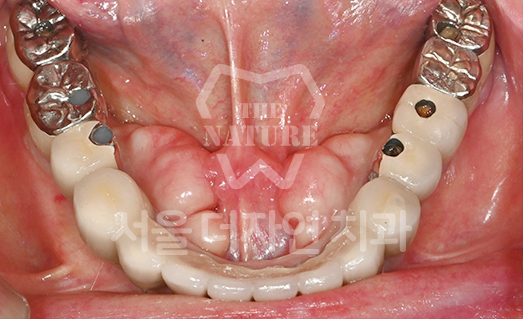

Full-Mouth Implant Restoration

Implant treatment for comprehensive full-arch restoration

This implant option is chosen to fully restore dental function. When missing teeth have been left untreated for an extended period,

the alveolar bone volume in both the maxilla and mandible is often insufficient. Therefore, a precise surgical plan must be established

with careful consideration of each patient's overall health condition.

• BEFORE: 2022.12.15

• AFTER: 2023.02.23